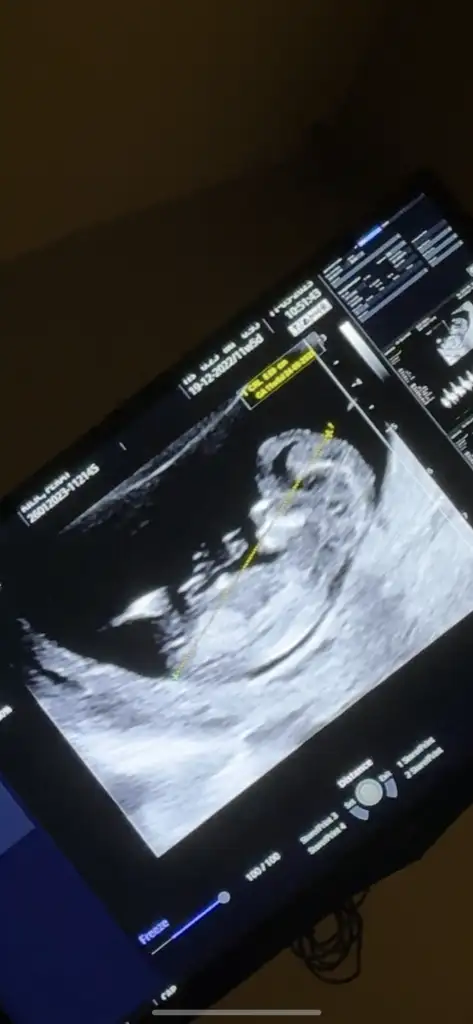

sizce 13-14. Haftalarda erkek bebeklerde çıkıntı mutlaka oluyor mu, bu durum yoksa kız mı denir doktorum çıkıntı göremediği için kız diyo

Eklentiler

• 9FF64C99-4E71-4CE4-BEBB-6390F544781D.webp

9FF64C99-4E71-4CE4-BEBB-6390F544781D.webp

13,9 KB · Görüntüleme: 83